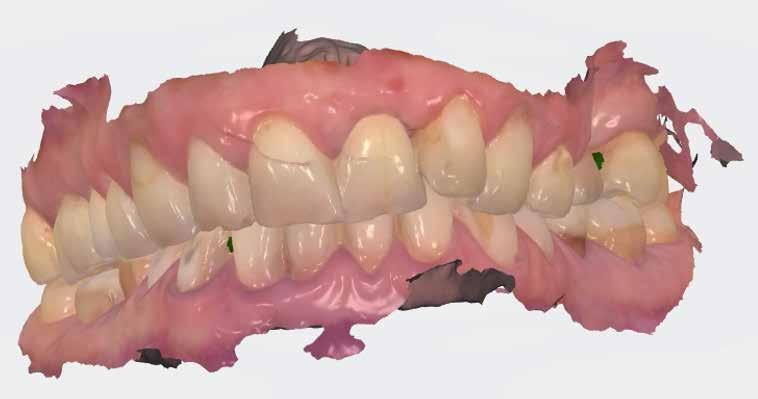

Esetbemutatás

2015-ben egy 47 éves férfi páciens állkapocs-ízületi panaszai miatt kereste fel a rendelőnket. Ezen felül esztétikai problémát jelentett számára, hogy az egyik felső nagymetszőfogán lévő héj eltört (1-3. ábrák). A klinikai és radiológiai vizsgálatot követően megállapítható volt, hogy a páciens kifejezett bruxizmusa miatt csökkent a harapási magassága, és jelentős mennyiségű saját foganyagot abradált el (4. ábra)

Szájterpesz használata mellett digitálisan intraorális fotók készültek a páciensről mind frontális, mind laterális és okkluzális irányokból. További fotók is készültek a páciensről egy digitális tükörreflexes kamera segítségével (frontális és laterális irányból, valamint 45 o-os szögből). Mindkét állcsontról digitális lenyomat készült egy intraorális szkenner segítségével (Care stream 3500). A maximális-interkuszpidációs helyzetet (IKP) szintén a Carestream 3500-as készülék felhasználásával rögzítet -

A páciens a megkezdett kezelések folytatása miatt 2017ben ismét felkereste a rendelőnket (7. ábra). Ekkor egy új intraorális lenyomatvétel történt (Carestream 3600).

A fogak preparálásához egy új mock-upot készítettünk háromdimenziós nyomtató segítségével (SolFlex, VOCO) bisz-akrilátból (Structur 3). A mock-up elkészítéséhez felhasznált sablont vákuum technológia segítségével hoztuk létre (V-Print ortho, VOCO). A mock-up felhelyezését követően a páciens fogait minimál invazív módon készítettük elő (8. ábra).

A már előzetesen preparált felső frontfogak csiszolt csonkjainak megtartottuk az eredeti formáját. Az alsó és felső őrlőfogak preparációja nem volt szükséges (1.7-1.4, 2.4-2.7, 3.7-3.4, 4.4-4.7), az alsó kismetsző fogakat minimál invazív módon készítettük elő. Az előkészítést követően új digitális lenyomat készült. Az így kapott digitális adatokat továbbítottuk a fogtechnikai laboratóriumba (9. ábra). A virtuális modellt ezek alapján hozták létre (AnatomicLab), és a minta elkészítéséhez szükséges STL fájlt továbbították egy háromdimenziós nyomtatóra (SolFlex 650, VOCO), amely segítségével elkészítették az új mintát (V-Print model, VOCO).

A végső restaurátumokat (héjakat és koronákat) Ce-

ramill Mind tervező program segítségével (AmannGirrbach) digitálisan megtervezték, majd frézgép segítségével (CeramillMotion 2, AmannGirrbach) li thium-diszilikát tömbökből (VITABLOCS TriLuxe forte for CeramillMotion 2, AmannGirrbach) kifaragták (10. ábra). Miután a fogpróba során ellenőrizték és megfelelőnek találták a pótlások széli záródásának a pontosságát, valamint az elkészült restaurátumok esztétikai megjelenését, ezután egy ajak- és szájterpesz került felhelyezésre (OptraGate, IvoclarVivadent).

A koronákat (1.3-1.1 és 2.1-2.3) és a héjakat (1.7-1.4, 2.4–2.7, 3.7-3.1, 4.1–4.7) fényrekötő adhezív rendszerrel rögzítették a pillérfogakhoz (Futurabond U ésBifix QM, VOCO). A polimerizációhoz egy nagy teljesítményű LED polimerizációs lámpát használtak (Celalux 3, VOCO), (1112. ábrák).

A kifolyó ragasztóanyagot ezt követően eltávolították, majd az okklúziót a T-Scantechnológia (Tekscan) segítségével ellenőrizték, majd a szükséges mértékben korrigálták. A véglegesen rögzített kerámiapótlás védelme érdekében a páciensnek a továbbiakban egy kivehető, átlátszó műanyag fogvédő sínt kellett viselnie. A pótlásokat 6 hónap múlva ellenőrizték. Az át adott fogpótlások stabilan rögzültek, és nem találtunk sérülésekre, repedésekre utaló jeleket (13-15. ábrák). A páciens arról is beszámolt, hogy a harapás megemelése óta megszűntek az őt rendszeresen gyötrő fejfájásai.